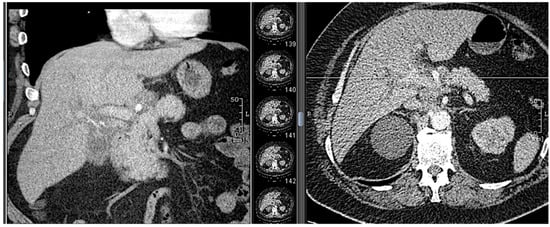

18.02: Contrast-enhanced CT demonstrated only mild hilar bile duct dilation, with no mass or lymphadenopathy (Figure 3).

CT at readmission: No significant interval change, plastic stent in situ, no evidence of ductal dilation or masses (Figure 7).

Figure 3. CT scan (18.02.2025): discrete hilar duct dilation, no visible mass.

Figure 7. CT scan (1.03.2025): no duct dilation, stent in situ, no new findings. A: anterior.